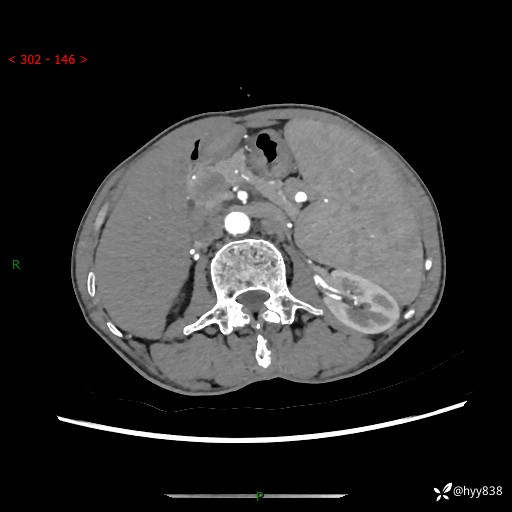

老年男性,脾大并脾脏弥漫粟粒状低密度,淋巴瘤 VS 肉芽肿 VS 血管瘤---结果公布

简要病史: 患者于3月前无明显诱因出现脾大,伴腹部轻微不适,具体不详,无腹痛、腹泻、腹胀,无头晕、头痛、乏力,无恶心、呕吐、呕血,无胸闷、气短、胸痛不适

上腹部CT平扫+增强